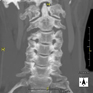

- TC Columna cervical

Prueba radiológica que consiste en obtener imágenes de las vertebras cervicales de alta definición anatómica mediante el empleo de un equipo de TC (Tomografía Computarizada). Indicaciones: cervicalgia sin/con irradiación a brazos, traumatismo.

Prueba radiológica que consiste en obtener imágenes de las vértebras cervicales de alta definición anatómica mediante el empleo de un equipo de TC (Tomografía Computarizada). Indicaciones: dolor cervical sin/con irradiación a brazos, traumatismo, malformaciones congénitas.